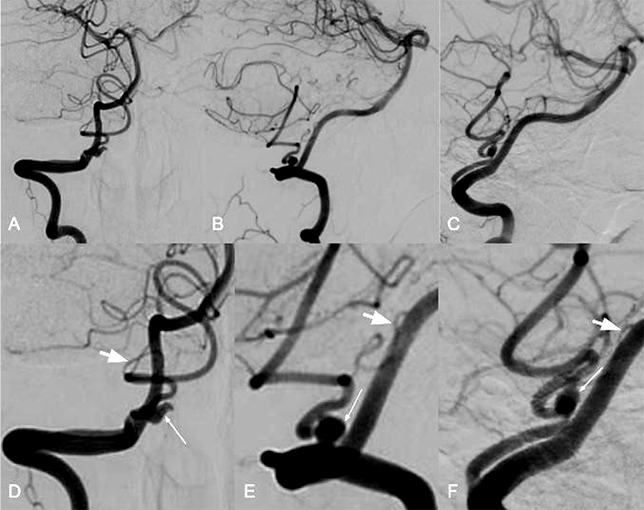

Селективная правосторонняя вертебральная ангиография

Аневризма задней оболочечной артерии — редкая патология. Разрыв такой аневризмы может привести к серьезным последствиям для здоровья больного. Для хирургического лечения используют микрохирургические и внутрисосудистые методы. В стационар РНХИ им. проф. А.Л. Поленова поступила пациентка 19 лет на 21-е сутки после субарахноидально-вентрикулярного кровоизлияния из аневризмы правой задней оболочечной артерии. При поступлении предъявляла жалобы на головную боль. В неврологической картине была мозжечковая симптоматика в виде атаксии верхних конечностей. По данным церебральной ангиографии выявили анастомоз между правой задней оболочечной артерией и гипоплазированным р1-сегментом правой задней нижней мозжечковой артерии дистальнее аневризмы. Внутрисосудистым методом выполнили окклюзию аневризмы отделяемой микроспиралью. Пациентку выписали на третьи сутки на амбулаторное наблюдение с полным регрессом неврологической симптоматики. На контрольной церебральной ангиографии через 3 мес. отметили тромбоз аневризмы с несущим сегментом артерии, а также перестройку основного кровотока данного бассейна через ранее гипоплазированную заднюю нижнюю мозжечковую артерию. В литературе нашли лишь 9 подобных наблюдений. По нашему мнению, внутрисосудистое лечение данной патологии эффективно и безопасно, а анастомоз дистальнее аневризмы позволил избежать нарушения кровоснабжения в сосудистом бассейне пораженной артерии.